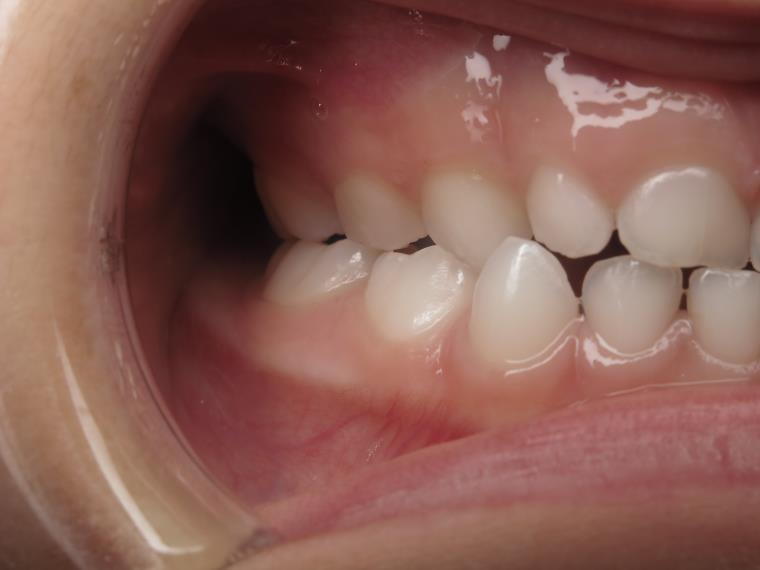

Sélectionnez les différentes étapes du traitement pour comparer et analyser la dentition du cas clinique.

surveillance évolution de la dentition en cours